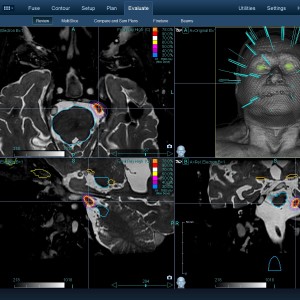

Στις παρακάτω φωτογραφίες θα δείτε παραδείγματα πλάνων θεραπείας καρκινικών όγκων με CyberKnife. Παρατηρήστε πόσο κοντά στους υγιείς ιστούς βρίσκονται οι καρκινικοί όγκοι που χρειάζεται να ακτινοβοληθούν. Μόνο με το CyberKnife και το προσωπικό πλάνο θεραπείας, μπορούν να ακτινοβοληθούν οι όγκοι χωρίς να πληγούν οι παρακείμενοι υγιείς ιστοί.

Μόνο με το CyberKnife και την κατάλληλη σχεδίαση της θεραπείας από έμπειρο νευροχειρουργό, μπορεί να ακτινοβοληθούν οι όγκοι χωρίς να επηρεαστούν από την ακτινοβολία οι υγιείς ιστοί. Αυτό εξασφαλίζει τη μέγιστη δυνατή απόδοση της ακτινοχειρουργικής θεραπείας των όγκων.

Ο νευροχειρουργός Λέκας Λεωνίδας έχει τη μεγαλύτερη εμπειρία στην Ελλάδα στο σχεδιασμό θεραπειών στερεοτακτικής ακτινοχειρουργικής όγκων του εγκεφάλου και του νευρικού συστήματος σε CyberKnife. Ο σχεδιασμός του πλάνου θεραπείας προϋποθέτει άριστη γνώση της ανατομίας και της απεικόνισης του κεντρικού νευρικού συστήματος έτσι ώστε να επιτευχθεί το βέλτιστο θεραπευτικό αποτέλεσμα με τη μέγιστη δυνατή προστασία των ευαίσθητων δομών.

Με κόκκινο χρώμα περιγράφεται η περιοχή του όγκου.

Με μπλε, κίτρινο και πράσινο χρώμα περιγράφονται οι υγιείς ιστοί που δεν πρέπει να ακτινοβοληθούν.

Παρατηρήστε πόσο κοντά βρίσκεται ο όγκος με τους υγιείς ιστούς.

Παρατηρήστε τις πάρα πολλές δέσμες του CynerKnife που ακτινοβολούν τους όγκους από διαφορετικές γωνίες ώστε να μην προσβληθούν από την ακτινοβολία οι υγιείς ιστούς.